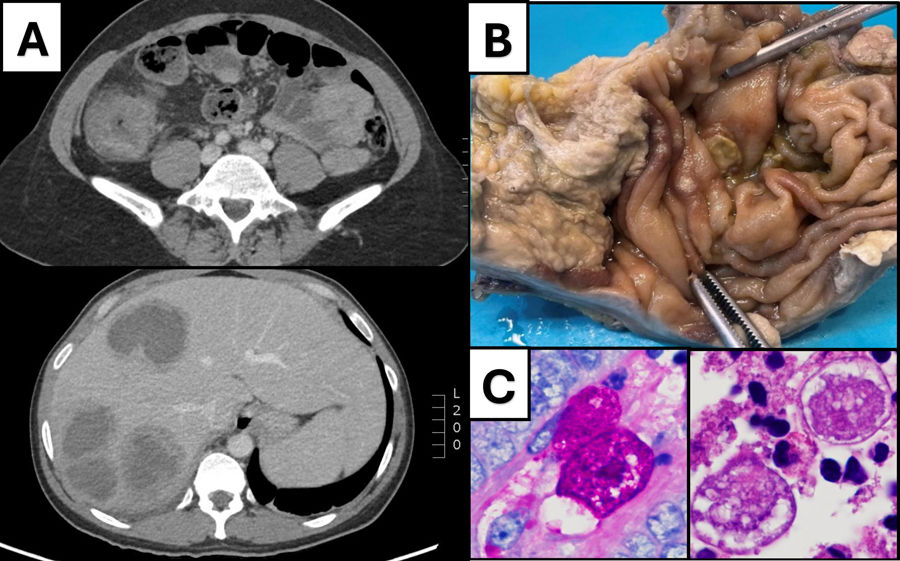

Masa colónica con múltiples lesiones hepáticas: no siempre es cáncer colorrectal

Colonic mass with multiple hepatic lesions: not always colorectal cancer